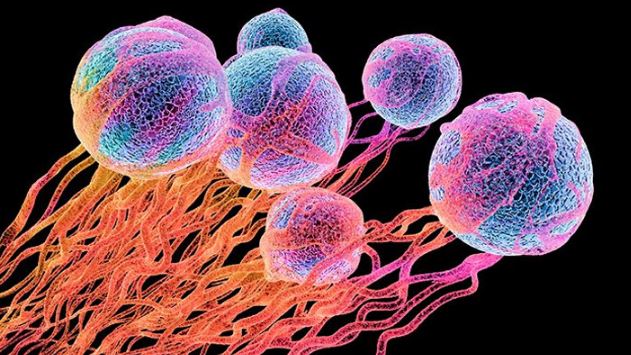

প্রবাস বাংলা ভয়েস ডেস্ক :: পাকস্থলীর ক্যান্সার সবচেয়ে জটিল...